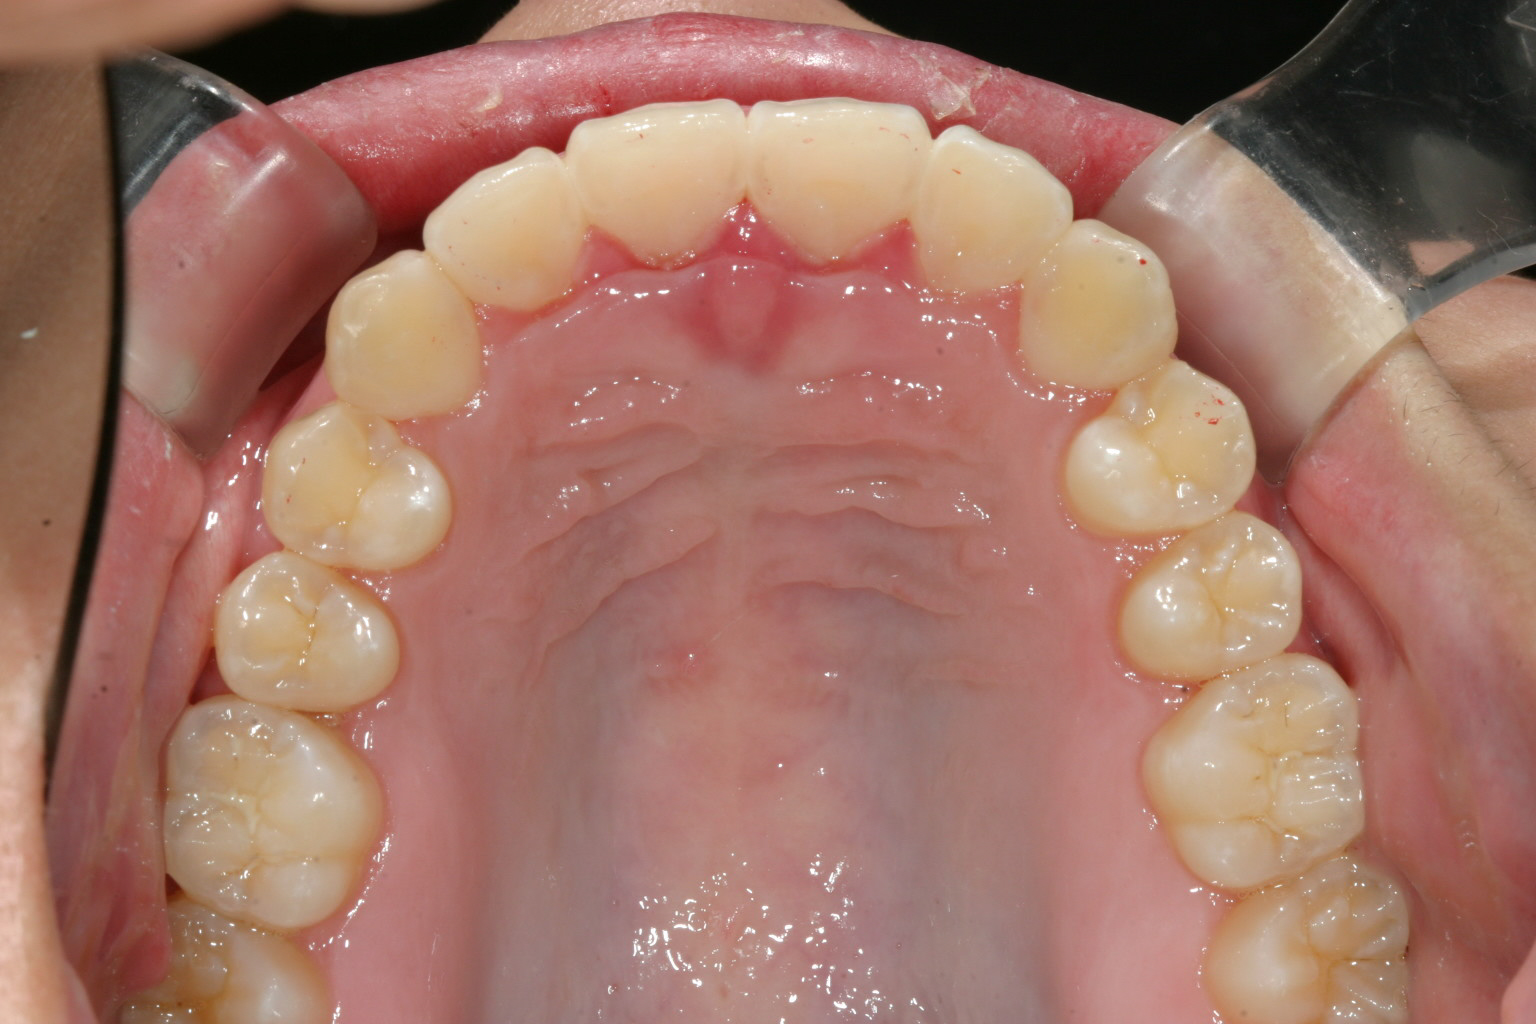

こちらのケースは上下顎前突の改善です。

上下顎とも臼歯部から前歯部にかけて最大限にIPR(歯と歯の間を削合)を行いました。

結果としてここまで出っ歯が引き込みました。

この様なケースにはインビザライン矯正で前もってどこにどれだけの隙間を開ければいいかをコンピューターで計測出来るのがいいですね~